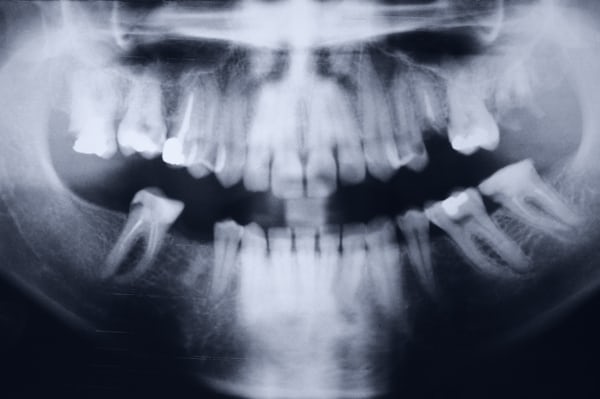

Cirugía oral en León Gto

La cirugía oral se realiza con precisión y cuidado, incluyendo extracciones complicadas y procedimientos quirúrgicos menores. El objetivo es minimizar las molestias y acelerar la recuperación, acompañándote en cada paso del proceso.

Si tienes molestias con muelas del juicio o dientes retenidos, una valoración oportuna puede evitar dolor, inflamación y futuros problemas dentales.

Extracción dental en León Gto

Extracciones Dentales en León Gto

Cuando un diente está gravemente dañado por caries, infecciones, fracturas o enfermedad periodontal, puede ser necesario extraerlo. También se extraen restos radiculares y muelas del juicio que causan dolor, infección o apiñamiento.

Se emplean técnicas modernas y seguras para garantizar que la extracción sea lo más rápida, cómoda y controlada posible, reduciendo molestias y favoreciendo una recuperación adecuada.

Endodoncia en León Gto

Endodoncia

La endodoncia se realiza cuando la pulpa dental se inflama o infecta, generalmente por caries profundas, traumatismos o fracturas. Este tratamiento permite conservar el diente natural, eliminando la infección y evitando su extracción.

Se utilizan tecnologías avanzadas como localizadores apicales, radiografía digital y sistemas rotatorios para lograr tratamientos precisos, seguros y duraderos.